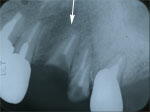

3.初診時X線写真

2年前には十分長かった歯根が、こんなにも短くなっていま

した。

抜歯はどうしても避けたいとの希望でした。 |